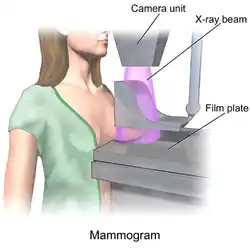

Mammography

Mammography is the process of using low-energy X-rays (usually around 30 kVp) to examine the human breast, which is used as a diagnostic and screening tool. The goal of mammography is the early detection of breast cancer, typically through detection of characteristic masses and/or microcalcifications.

In addition to diagnostic purposes, mammography has interventional utility in stereotactic biopsies to precisely locate and find the area of concern and guide the biopsy needle to this precise location. This ensures that the area biopsies correlates to the abnormality seen on mammogram. It is called stereotactic since it uses images taken from two different angles of the same location. A biopsy is indicated when small accumulations of calcium are seen on mammogram, but cannot be felt on physical exam and do not appear on ultrasound.